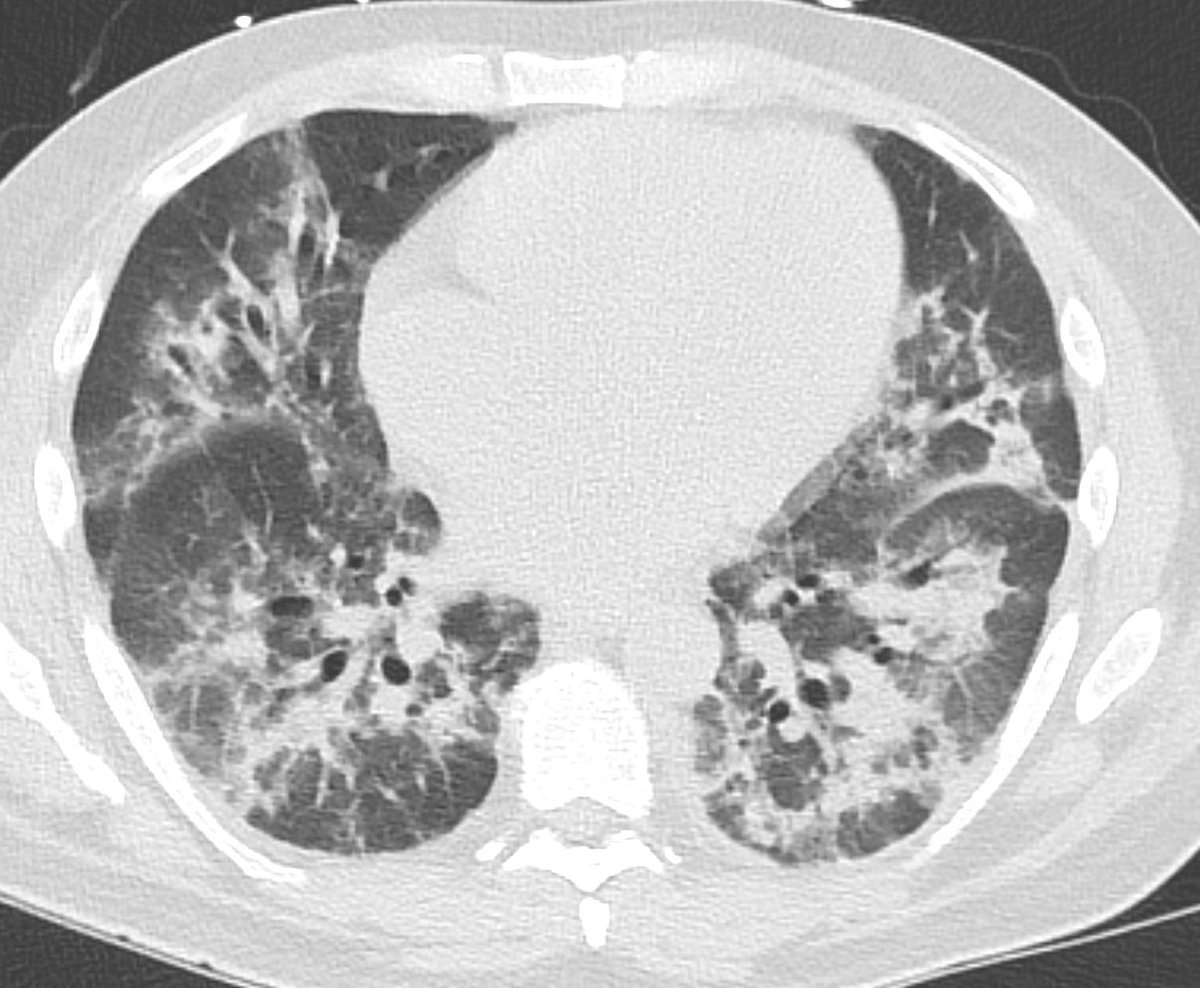

Here are the lung windows, showing pretty typical right lower lobe pneumonia. Does this change your thinking about the first image? Note that there is no interstitial edema in the RLL or pleural effusion.

If we look at lung windows, decreased perfusion through the right lung can be appreciated as diffusely decreased density of the right lung. Interestingly this involves much more lung than just the area of pneumonia - here much of the right lung is affected.

Another important thing to think about here - if this was a big thrombus in the right inferior pulmonary vein, there would be significant interstitial edema/septal thickening in the right lower lobe, and probably an effusion. These are not present.